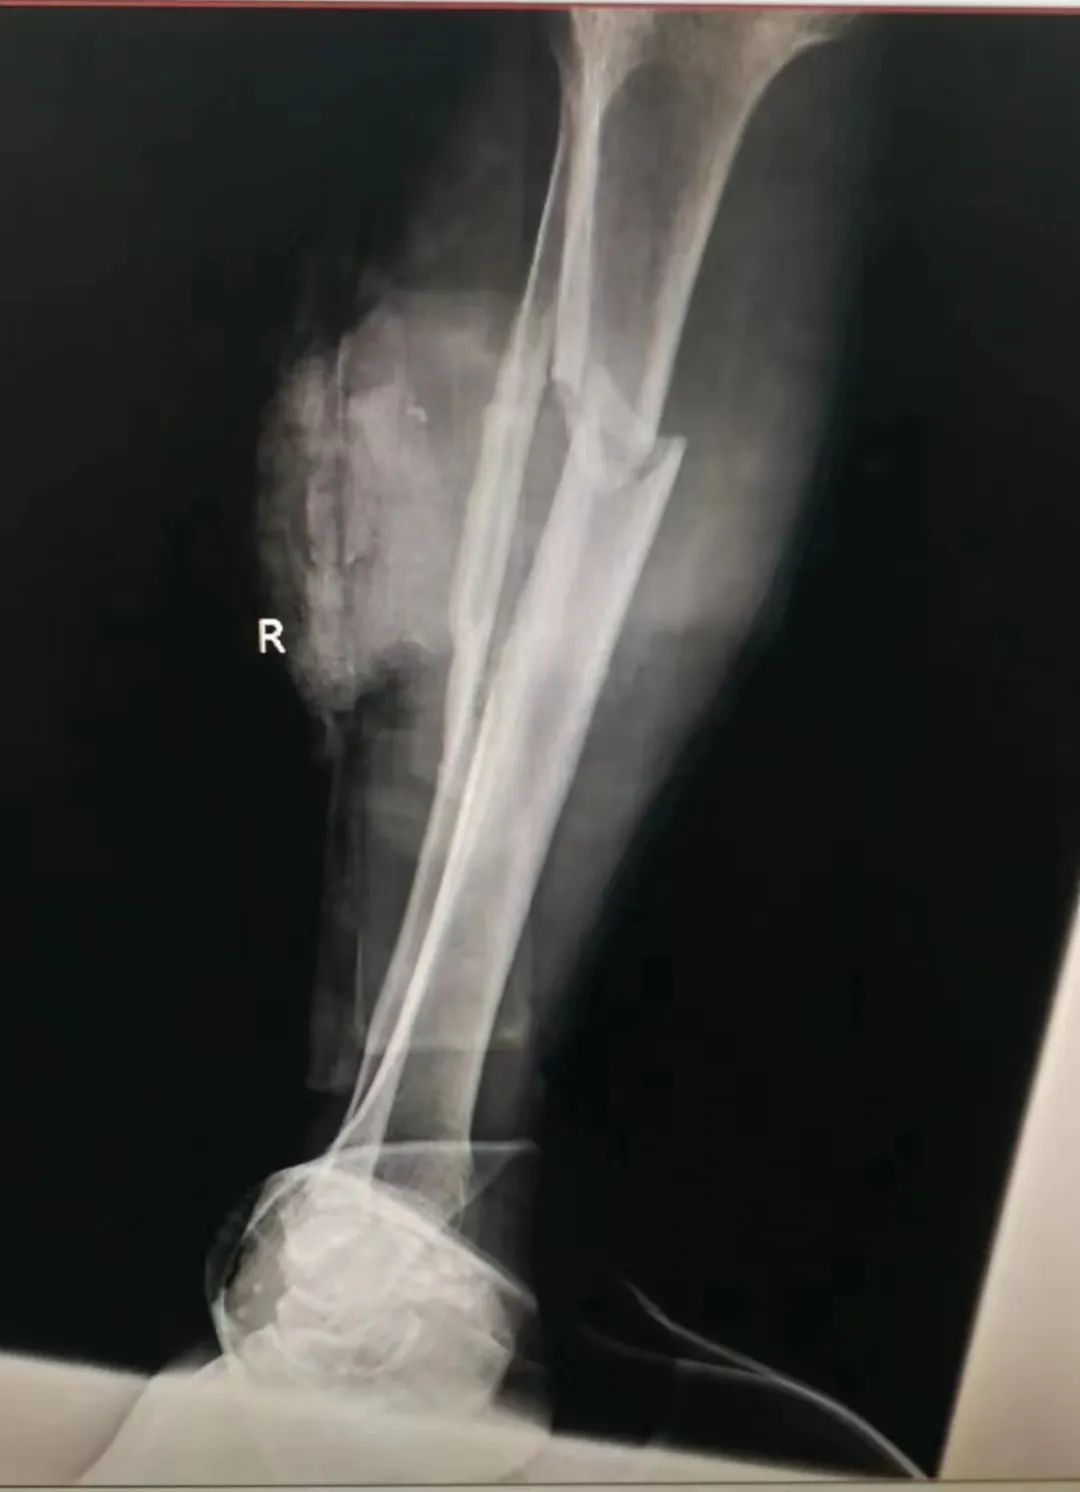

患者右小腿胫骨骨折x光片

“右小腿切割伤、胫骨开放性骨折、腓骨粉碎性骨折、伤口内可见大量挫烂的肌肉……”一个近8cm的斜型伤口横在伤者小腿前外侧,创伤巨大、肌肉大量挫烂且外翻,即使是已有近30年临床经验、处理过无数次四肢复杂损伤手术的陈汉东,看到这么大的创伤,内心都稍感发怵。意识到病情的严重性,待各项血液检查结果出来后,陈汉东表示:“立即手术!”